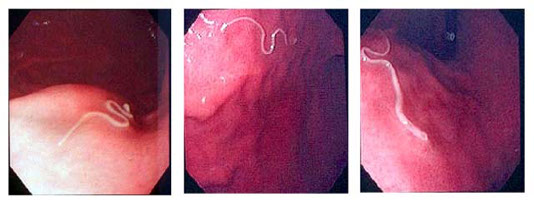

• Anisakiasis

S dermatitis

References

1. LLU notes